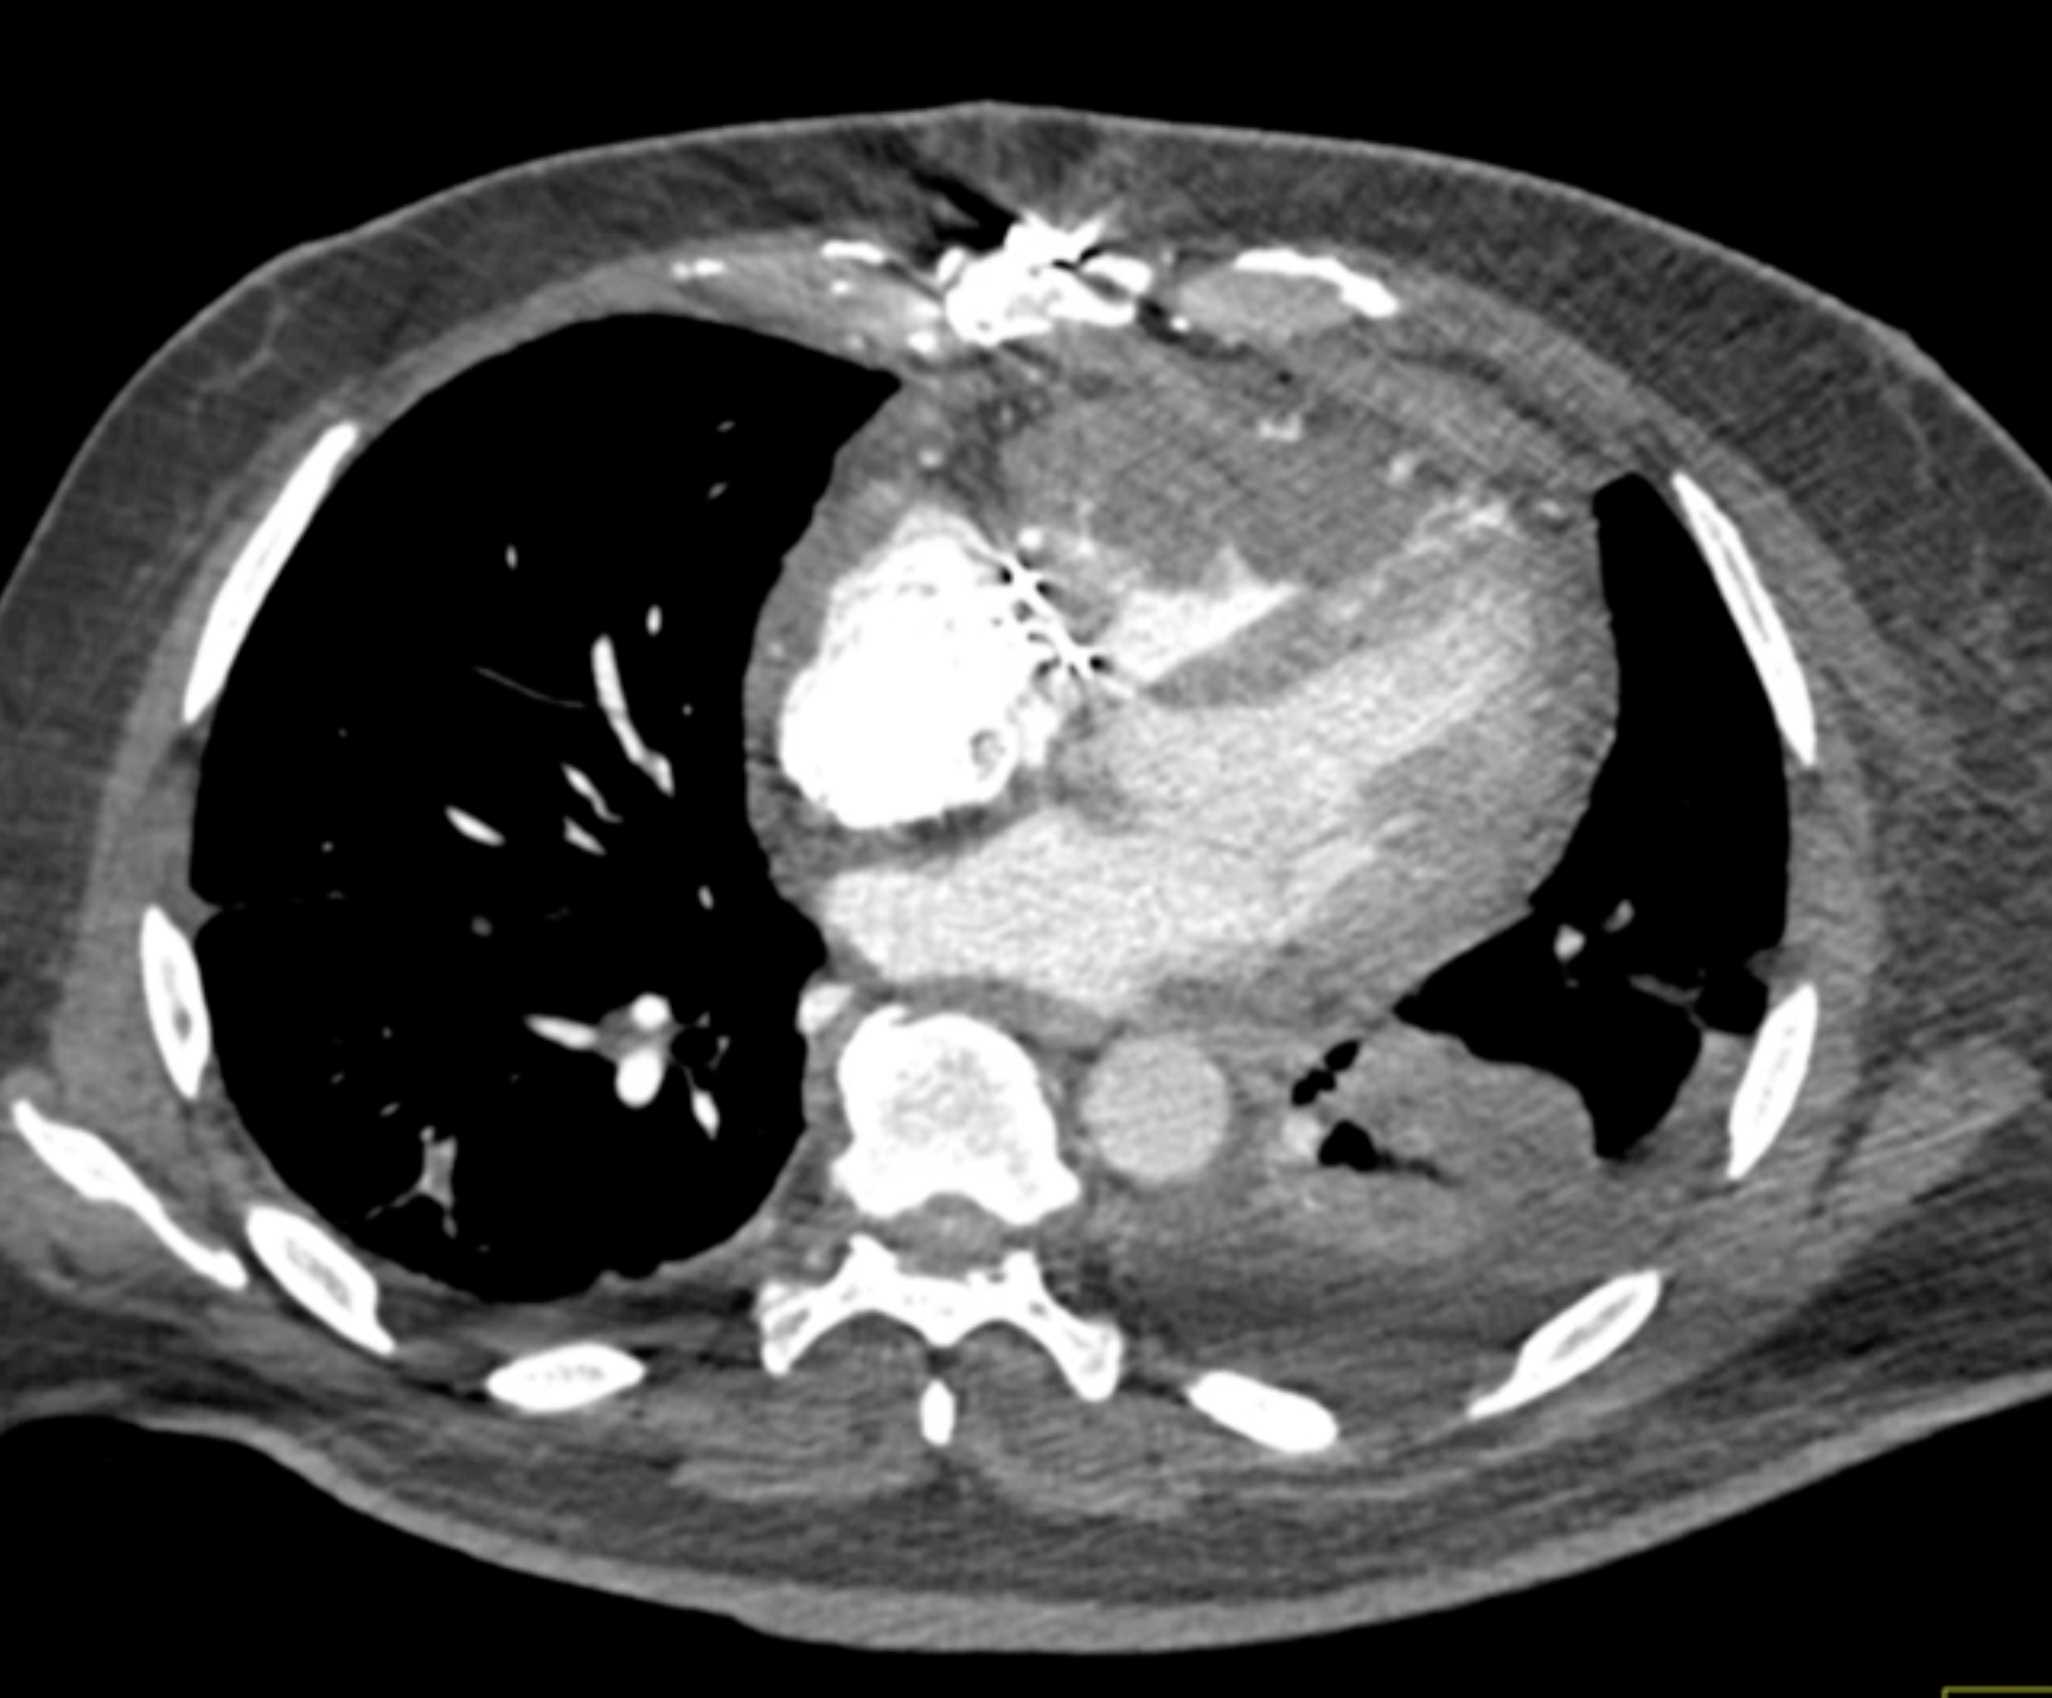

Primary Spindle Cell Carcinoma of the Right Ventricle